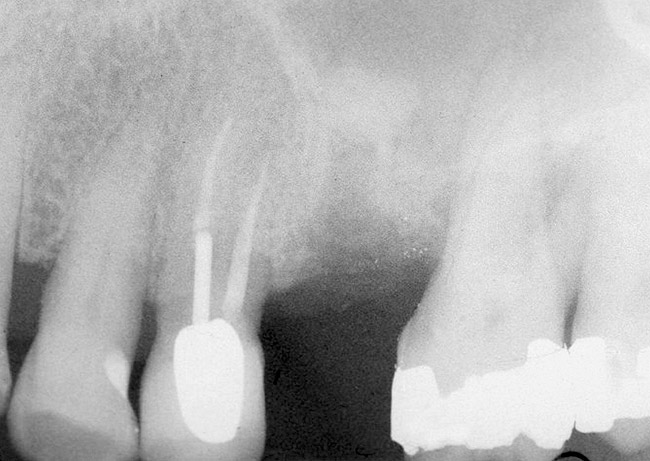

Recently, Jung et al20 indicated the total mean reduction in the grafted bone height was 1.9 mm 5 years after a transcrestal sinus floor elevation. It is not uncommon to detect that bone remodeling occurs over time (Figure 6 and Figure 7). In particular, bone that initially appears apical to the inserted implant resorbs and, subsequently, the osseous crest is found at the apex of the implant.

Figure 6  At site No. 14, a radiograph depicting the full "dome" of graft material apical to the implant.

Figure 6

Figure 7  Radiograph depicting a "flattening" of the dome that has taken place in the first year after the graft was performed. This shows consolidation of the graft and remodeling that takes place over time.

Figure 7